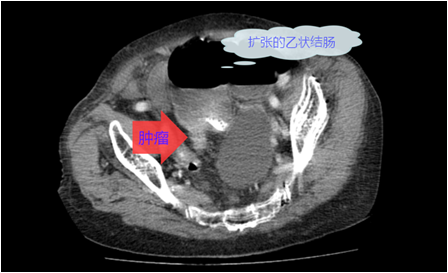

结直肠癌是我国常见的恶性肿瘤,患者就诊时多已为晚期或局部晚期。由于肿瘤瘤体巨大,侵犯邻近脏器,多个脏器受累,临床处理有一定困难。部分外科医生面对晚期结直肠癌时选择放弃手术。但事实上,多学科综合治疗能使晚期或局部晚期患者获得相对好的治疗结果,不应该轻易放弃合理的外科手术。对于肿瘤巨大但没有远处转移,有多脏器受累的患者,直接手术切除困难,可以考虑进行术前的辅助治疗。外科手术原则是在能够达到R0切除的基础上,尽量保留脏器的功能,进行合理的区域淋巴结清扫。

这老太太87岁,肠癌梗阻,病情较晚,在其他医院不敢做,准备放弃了,来我院经过处理后,微创手术解决问题。